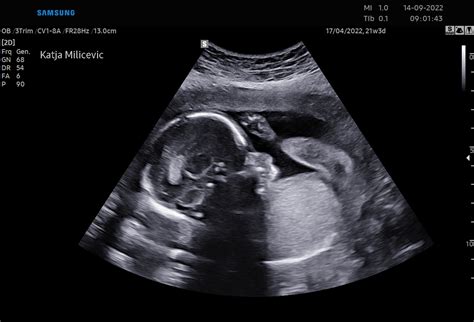

- 19.-20. teden: Možgani se intenzivno razvijajo, intenzivna rast ploda se nadaljuje. Tudi nosečnice, ki so prvič noseče, bodo morda že lahko prvič občutile gibe ploda. V tem času se običajno opravi morfološki ultrazvočni pregled ploda. Na koži se pojavi verniks - bela mastna zaščitna snov.